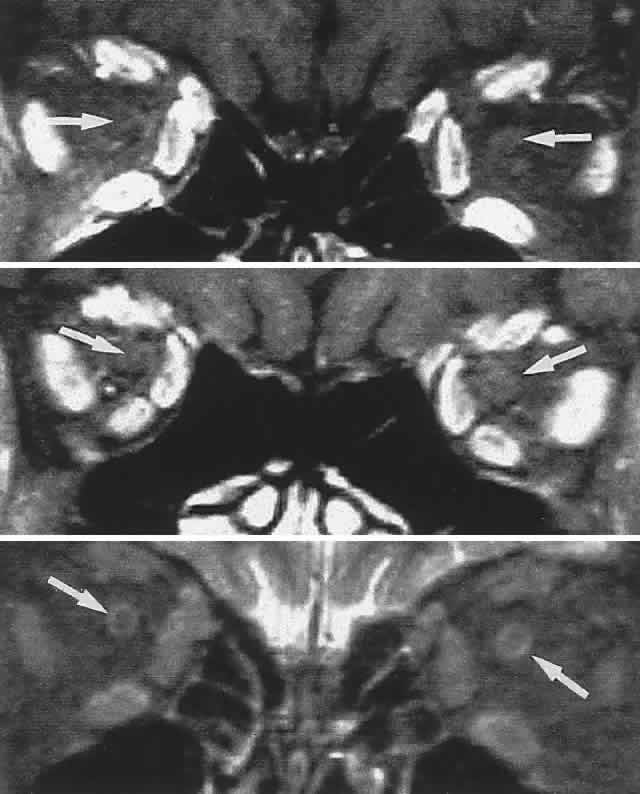

Now almost universally available, MRI is the preferable technique for imaging the soft tissue contents of the orbit, high-resolution 3-mm and thinner sections being available, as well as gadolinium contrast enhancement (Figs. 19, 20, and 21).

Fig. 19. MRI of orbits, axial sections. Top. T1-weighted: orbital fat is white (hyperintense), muscles are dark. Middle. Fat saturation with gadolinium through midorbit: orbital fat signal suppressed (dark), accentuates hyperintense muscles; note also choroid (small arrows). Bottom. Fat-saturation technique through superior aspect of orbit; note superior ophthalmic veins (arrows).

Fig. 20. MRI of orbits, coronal sections. Fat suppression. Top. Midorbit. Middle. Orbital apex. Bottom. T2-weighted. Arrows indicate optic nerve; note ring of CSF (bottom).